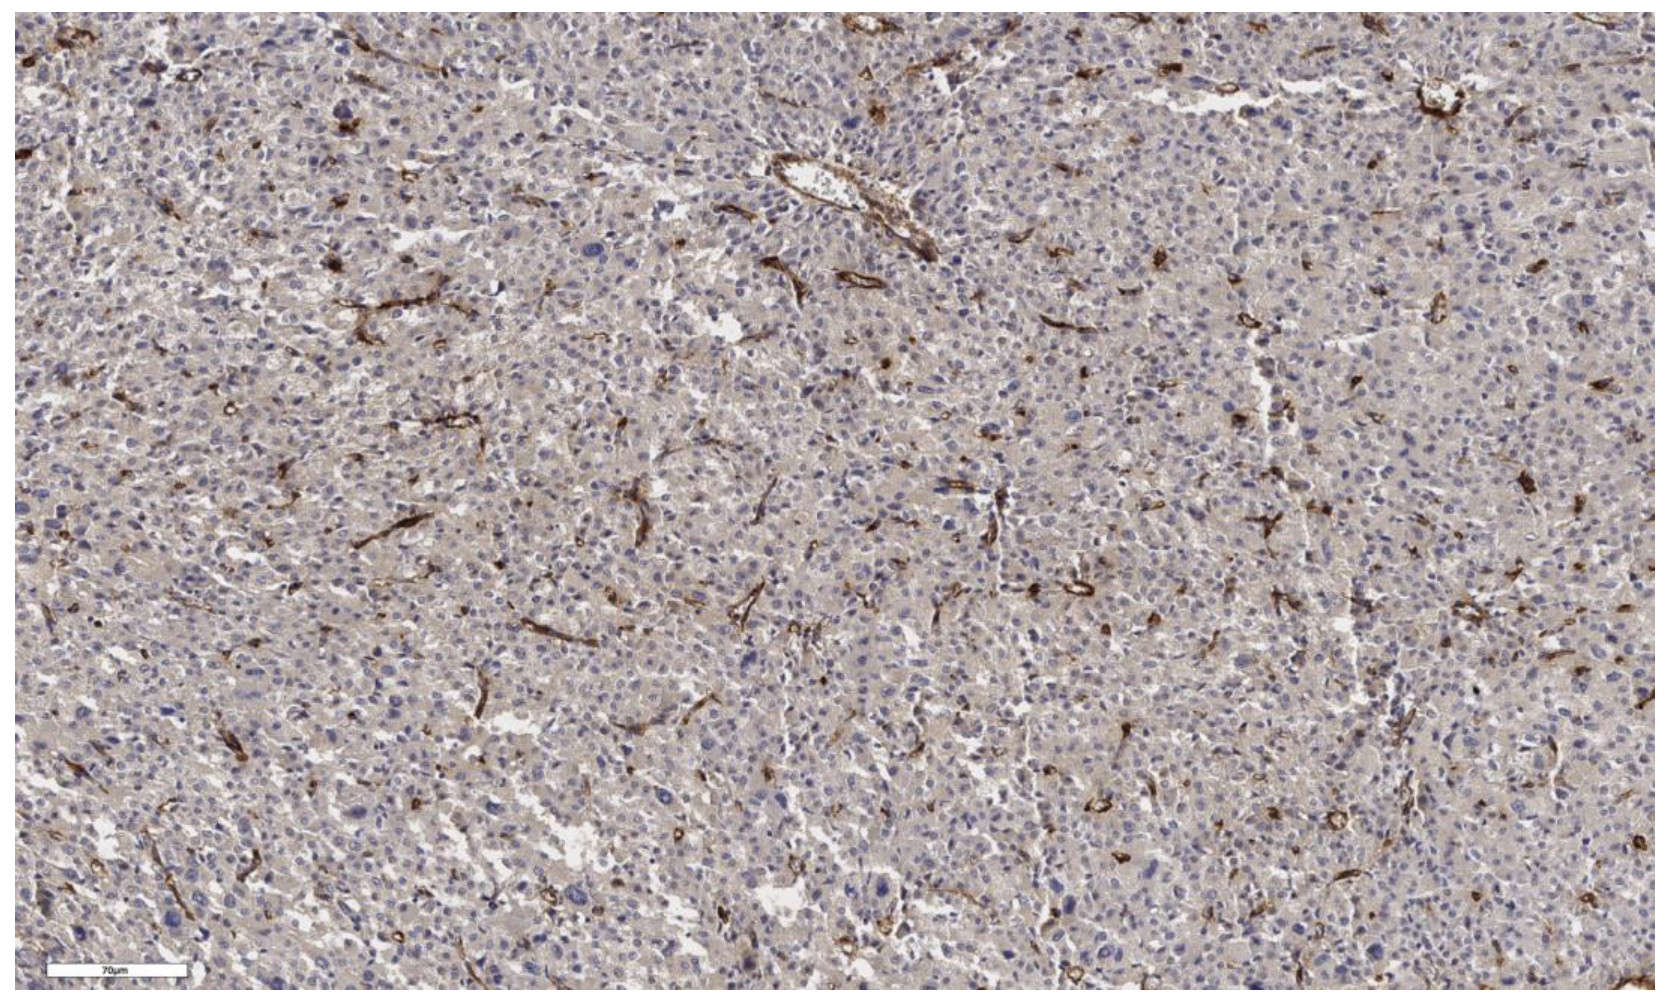

3.1. Analysis of CD90 Marker Expression

3.4. Analysis of Stem Marker Expression in Normal Adrenal Tissue